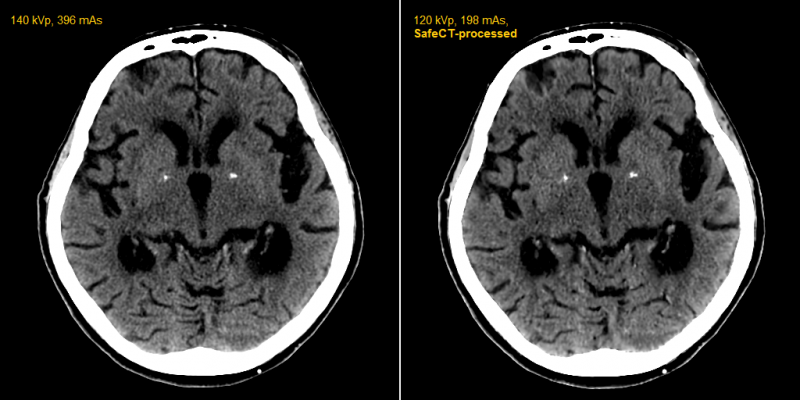

Using proprietary patented iterative volumetric image reconstruction algorithms, SafeCT delivers diagnostic image quality to studies acquired over a wide range of exposure parameters on any CT scanner. Its use eliminates the need to replace existing CT systems with newer and more expensive scanners to achieve similar results.

A single SafeCT can simultaneously serve multiple scanners in different locations. Its use is virtually transparent to department workflow. The noisy images are automatically sent from the CT console to SafeCT, which processes them and transfers the enhanced images in real time to the picture archive and communications system (PACS) and/or workstation without any intervention by the technologist.